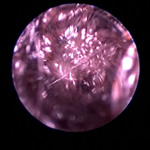

ポリープや腫瘤を伴う耳道炎と中耳炎

外耳炎が慢性化すると過形成、アポクリン腺腫瘍、炎症性ポリープ、鼻咽頭ポリープ(猫)などにより耳道が狭くなったり、閉塞することがあります。これが原因で外耳炎が治癒せず中耳炎に至るケースがよくあります。この状態になると生涯にわたり治療が必要になったり、根治には手術が必要になることもあります。